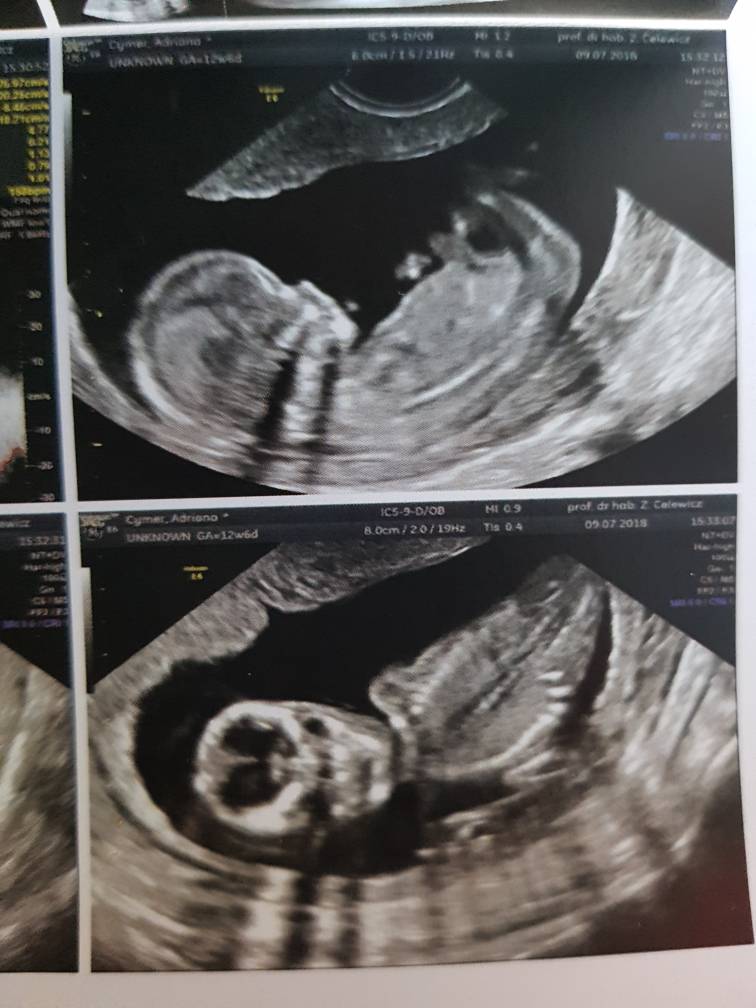

Mam 6.51cm taki już duży jestem :-)

Pięknie machałem do mamy i taty i ładnie współpracowałem z Panią doktor :-)

Pani doktor powiedziała, że wyglądam jej na chłopca i by się bardzo zdziwiła jeśli okazałoby się, że jestem dziewczynkątakże jak na razie zostaję Mateuszkiem[emoji170] [emoji7] Co mamie się zgadza bo tak czuje[emoji12]

na USG wszystko w porządku, jeszcze tylko trzeba poczekać na wyniki z krwi ale mama jest dobrej myśliZobacz załącznik 875479Zobacz załącznik 875480